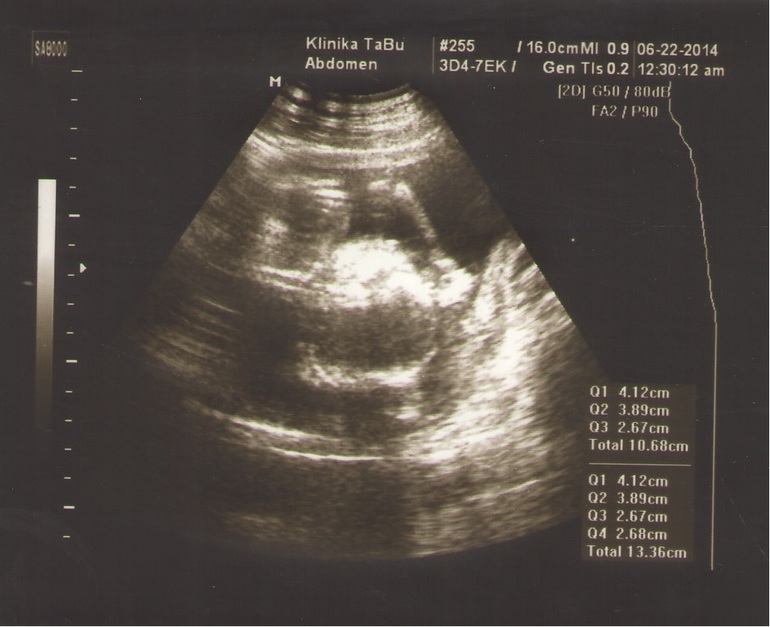

УЗИ, КТГ, доплерНам на узи делали три фото, с двумя разобрались, а вот с одним...ну никак не можем понять ничего, странное фото! Я вообще не ориентируюсь, где тут у моего ребенка что! Можете кто нибудь расшифровать и показать мне где что!!! Кому не трудно! Где профиль ребенка...голова вроде понятно что справа и то не факт.......смотрим смотрим с мужем а понять не можем, и так и сяк крутили!

то что ближе к левой части, большое белое — это головка, смотрит на вас, если присмотреться, то есть 2 черных шарика, один выше, другой под ним, это глазки, левее получается виден серый лоб, а правее все белое — это челюсти и подбородок. белая полоса сверху поду углом — это ручка. а большой шар справа и выше — это животик, черный шарик снизу в нем — это желудок. и рядом с желудком еще белая полоса горизонтально в верх — это ребра, а ниже белая палочка небольшая — это вторая ручка

фотография действительно не самая удачная, но продолжайте вглядываться! и вы найдете на лице глазки, особенно правый, его лучше видно, рядом с рукой ( сверху), рука к виску направлена, а вот левый (нижний) сложнее, он не ровно под верхним (правым), а чуть правее, так как головка под наклоном:))) а над глазиком даже надбровная дуга видна (у нижнего глаза левее темного пятна видна белая полоса) пытайтесь, вглядывайтесь:) и дорисовывайте в мыслях:)

Мне кажется,что лежит спинкой кверху. Справа голова,вниз-носик и сосет кулачек)))А на правую ручку опирается. Ножек почти не видно-очень расплывчато...

Мне тоже кажется, что слева ножки, внизу одна ручка, вверху вторая, посередине туловище, а голова повернута лицом к нам и вон глазки видно. А вообще, фотки конечно жесть))) Аппарат у них что ли старый там?

Мне тоже виднеется лицо пря по центру! Но что тогда справа круглое...))